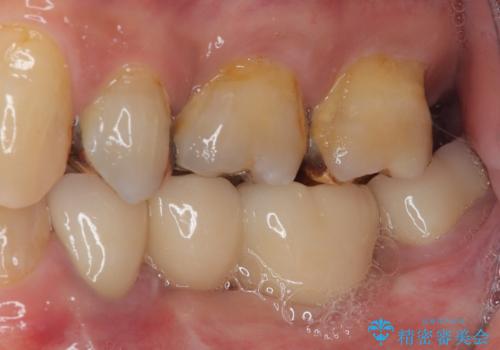

- 下顎両側の欠損と上顎前歯のデコボコを気にして来院された患者様です。

デコボコは今まで気にせずにいたそうですが、奥歯の欠損改善を機に、矯正治療に興味があるので、相談したいとのことでした。

奥歯に欠損が多く、矯正治療はやや難航することが予想されますが、患者様の希望もあり、上顎左右小臼歯を1本ずつ抜歯し、ワイヤー装置にて矯正治療を行うこととしました。

矯正歯科治療を行うに当たり、痛みや違和感を感じている歯の根管治療を行い、矯正治療中にインプラント埋入し、補綴治療と矯正治療を同時に終了できるように進めて行くこととしました。